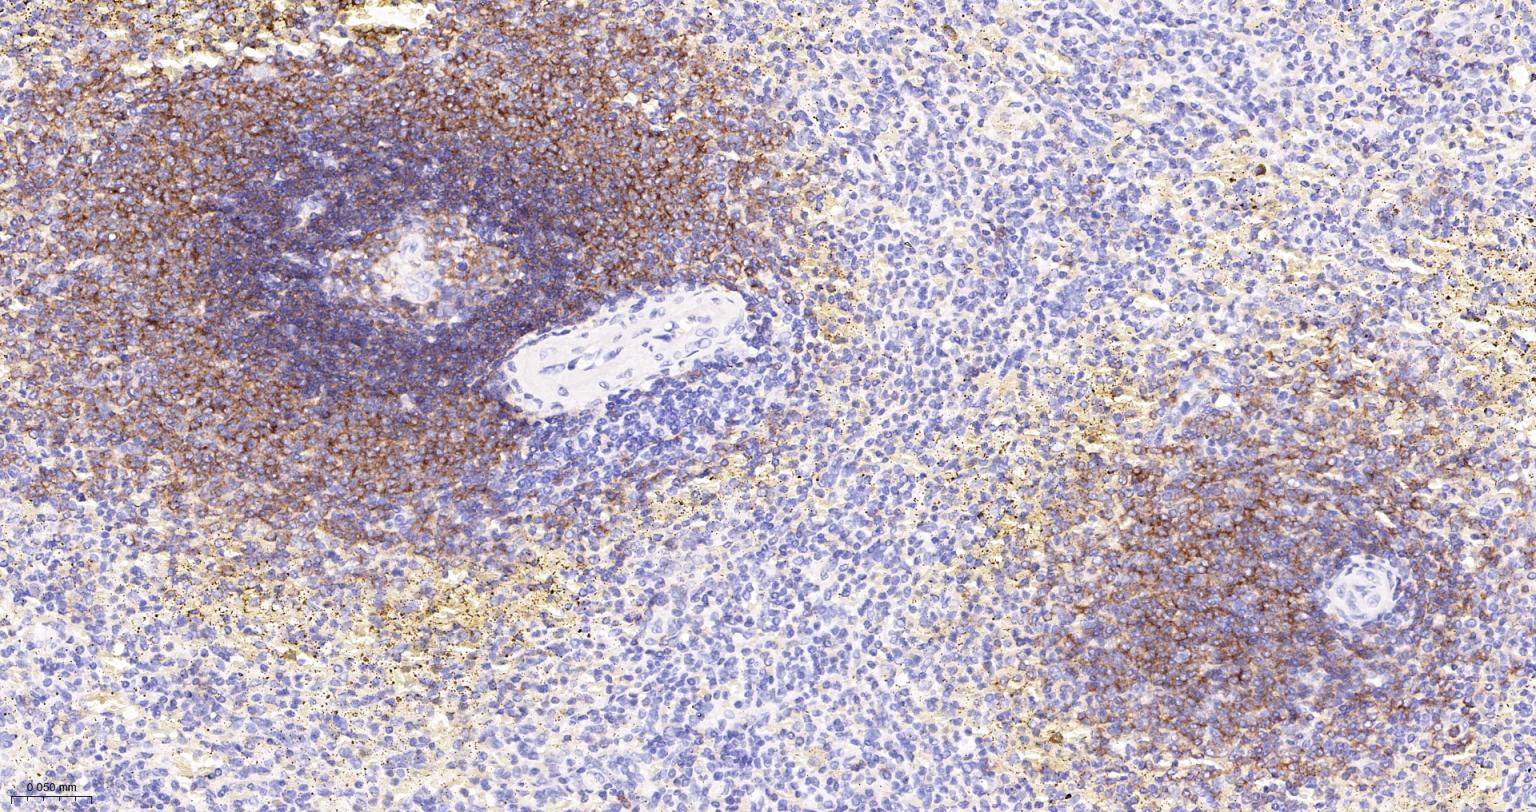

CD19 Recombinant Rabbit mAb

CD19是一种质膜蛋白质,参与信号传导作用。表达与前B细胞和成熟的B细胞膜表面,与B细胞的活化调节和发育调节相关,在T细胞和正常粒细胞上无表达。此抗体可以特异性识别CD19,主要用于标记正常B细胞及肿瘤性B细胞。

IHC-PHuman1:200-500